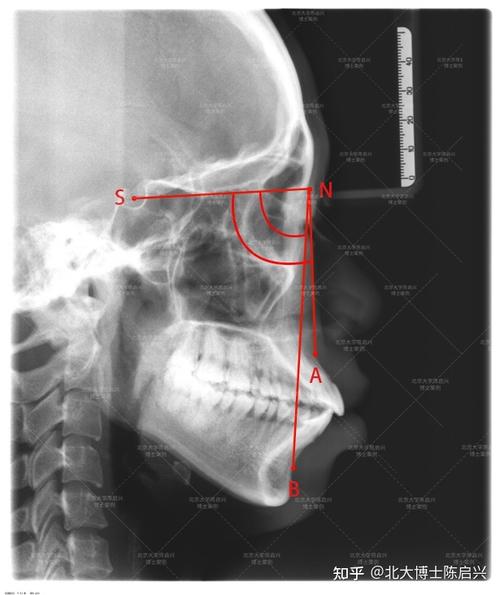

anb角的构成依赖于头颅侧位片上的三个标志点:

- A点(Subspinale,上齿槽座点):上颌骨前壁与梨状孔下缘的交点,位于上颌骨最前端,反映上颌基骨的位置。

- N点(Nasion,鼻根点):鼻额缝的最前点,位于颅底与前颅底的交界处,作为颅部的参考点。

- B点(Supramentale,下齿槽座点):下颌骨前颏联合部与下齿槽缘的交点,位于下颌骨最前端,反映下颌基骨的位置。

- 在X线片上精确标记A、N、B三点:N点通常位于鼻梁根部凹陷处;A点为上颌牙槽突最前点,与上颌中切牙牙根尖接近;B点为下颌牙槽突最前点,与下颌中切牙牙根尖接近。

- 连接N-A线(鼻根点至上齿槽座点的连线)和N-B线(鼻根点至下齿槽座点的连线),两条线在N点形成夹角,即为anb角。